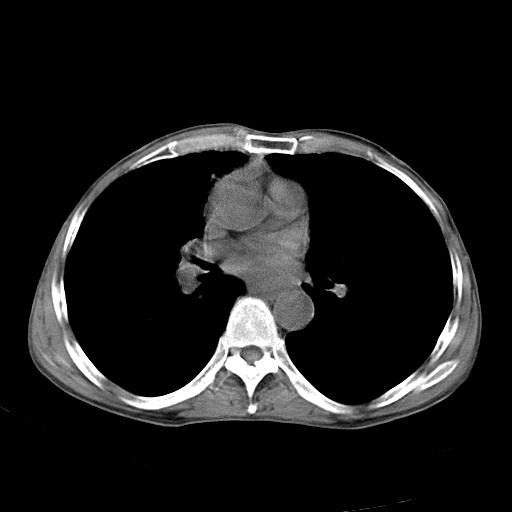

以下是引用苯小孩在2007-5-24 12:47:00的发言:[br]右侧肺门处不均匀密度软组织块影,远端肺组织见斑片模糊影,纵隔内淋巴结明显肿大,边界不清.<纵隔窗第12层面支气管内似见软组织结节>[br]考虑:1、右侧中央性肺癌并阻塞性肺炎并纵隔淋巴结转移可能性大.建议强化或纤支镜进一步检查.[br]2、隆突下淋巴结肿大/食道病变?请做鉴别检查.

以下是引用zhangzhongshou在2007-5-24 12:55:00的发言:[br]1、右肺中叶中心型肺癌并右肺门、隆突下、纵隔淋巴结转移。右肺中叶阻塞性肺炎。

以下是引用jw-830在2007-5-24 15:24:00的发言:[br][br] [br] 考虑右肺中央型肺癌并阻塞性炎症,右肺门及纵隔淋巴结转移。 [br] [br][br]